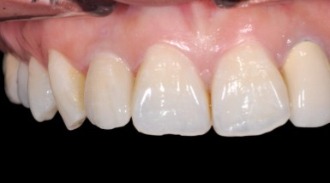

正式植牙假牙安裝

全瓷植牙假牙安裝,治療完成。正式植牙假牙有著比較多的細節,顏色與形狀也像真牙般逼真。

正式植牙假牙

顏色與形狀與都有較多的細節

客製化 二氧化鋯 連接器組合

仿真 植牙用 全瓷牙冠

客製化 二氧化鋯 全瓷連接器,避免牙齦產生黑色陰影

模仿自然牙齒的全瓷假牙安裝